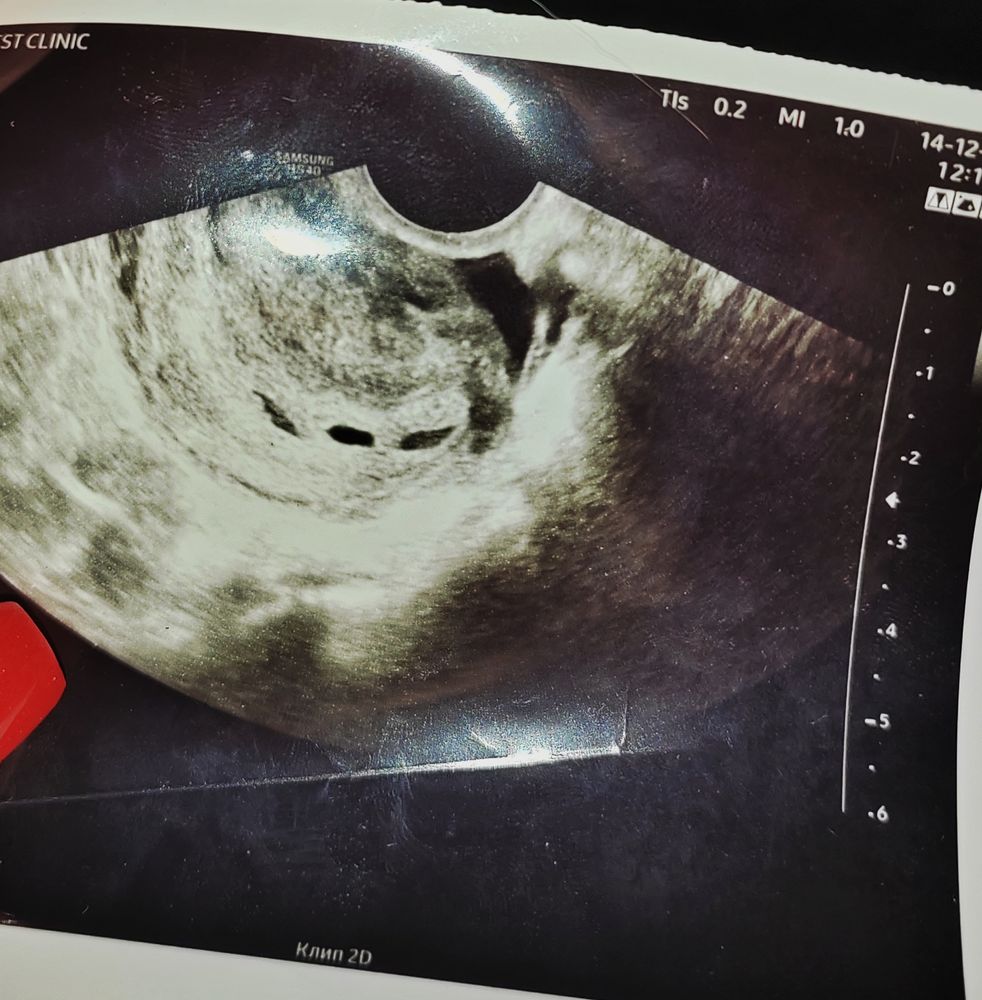

Помогите разобраться, где находится плод

в 6 недель уже внутри плодного яйца обычно видно желточный мешок хотя бы, иногда и эмбрион. тут ничего не понятно… нужно либо в другом месте переделать либо чуть подождать…

Yana Pepper, по снимку не понять тут

Вообще не вижу... Кадр неудачный какой-то